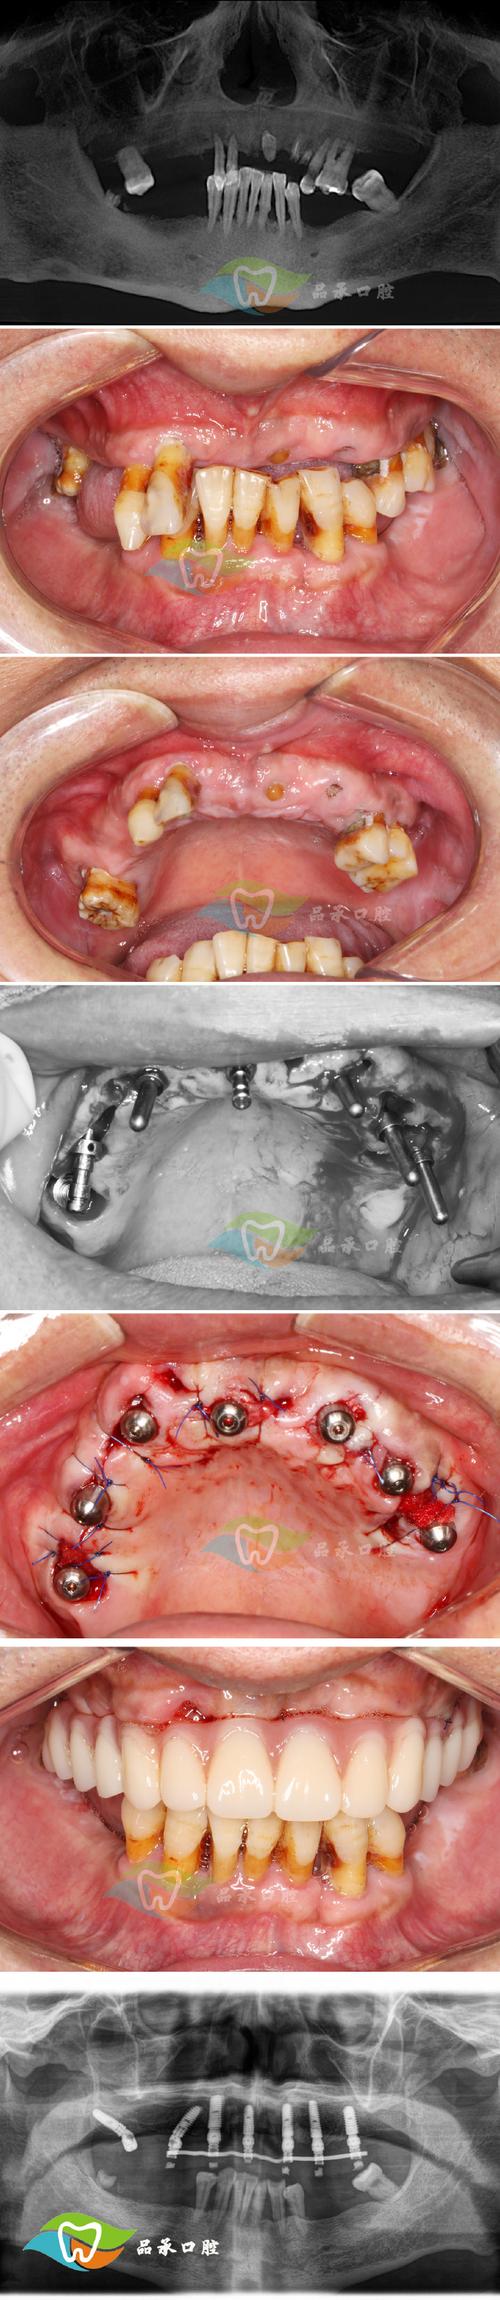

- 手术阶段:在全麻下完成颌骨截骨、移动、固定,手术时间约2-5小时,住院观察3-7天。